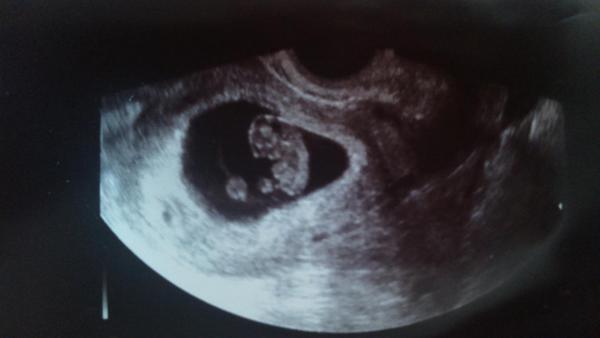

@delfi75 tady je naše "eskymo", říkala paní doktorka, že je to prý fakt krásný miminko🙂 nějak brzy🙂